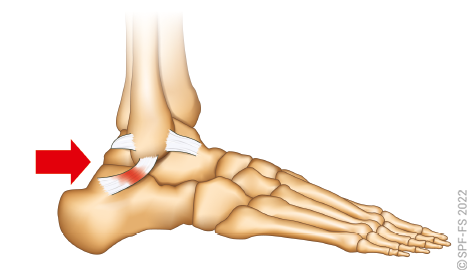

La hanche est l'articulation qui relie la cuisse au bassin. Le genou relie la cuisse à la jambe et la cheville la jambe au pied.

Ce dernier comporte cinq orteils numérotés de 1 à 5 de l'intérieur vers l'extérieur. Les phalanges sont numérotées de P1 à P3, dans le sens allant du talon vers l'ongle.